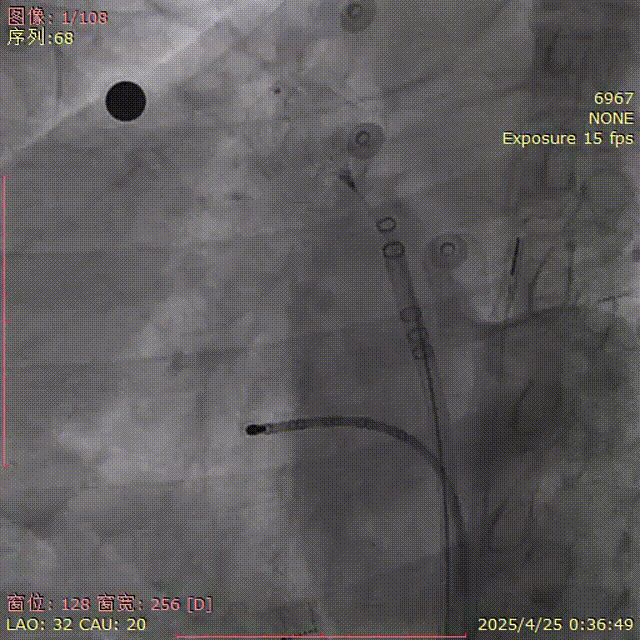

封堵器释放

释放后再造影

释放钢缆后造影,封堵器位置稳定,释放后形态良好

超声确认

封堵器位置良好,术后无心包积液